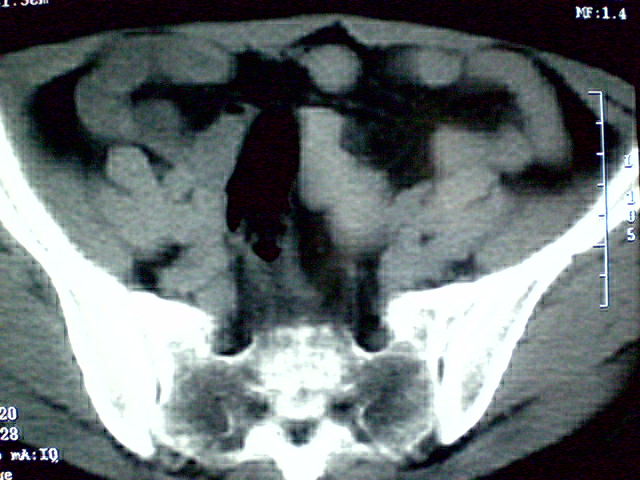

f 60y,b超提示脂肪瘤.[img][/img]

右侧附件囊性畸胎瘤,三种组织均见.

右侧附件囊性畸胎瘤.

那个高密度灶形状好象牙齿。典型,收藏了

脂肪密度肿块,内可见团块状影,典型皮样囊肿

的确比较典型的畸胎瘤!不过,应该确切的说是盆腔畸胎瘤,右侧附件来源的可能性比较大。